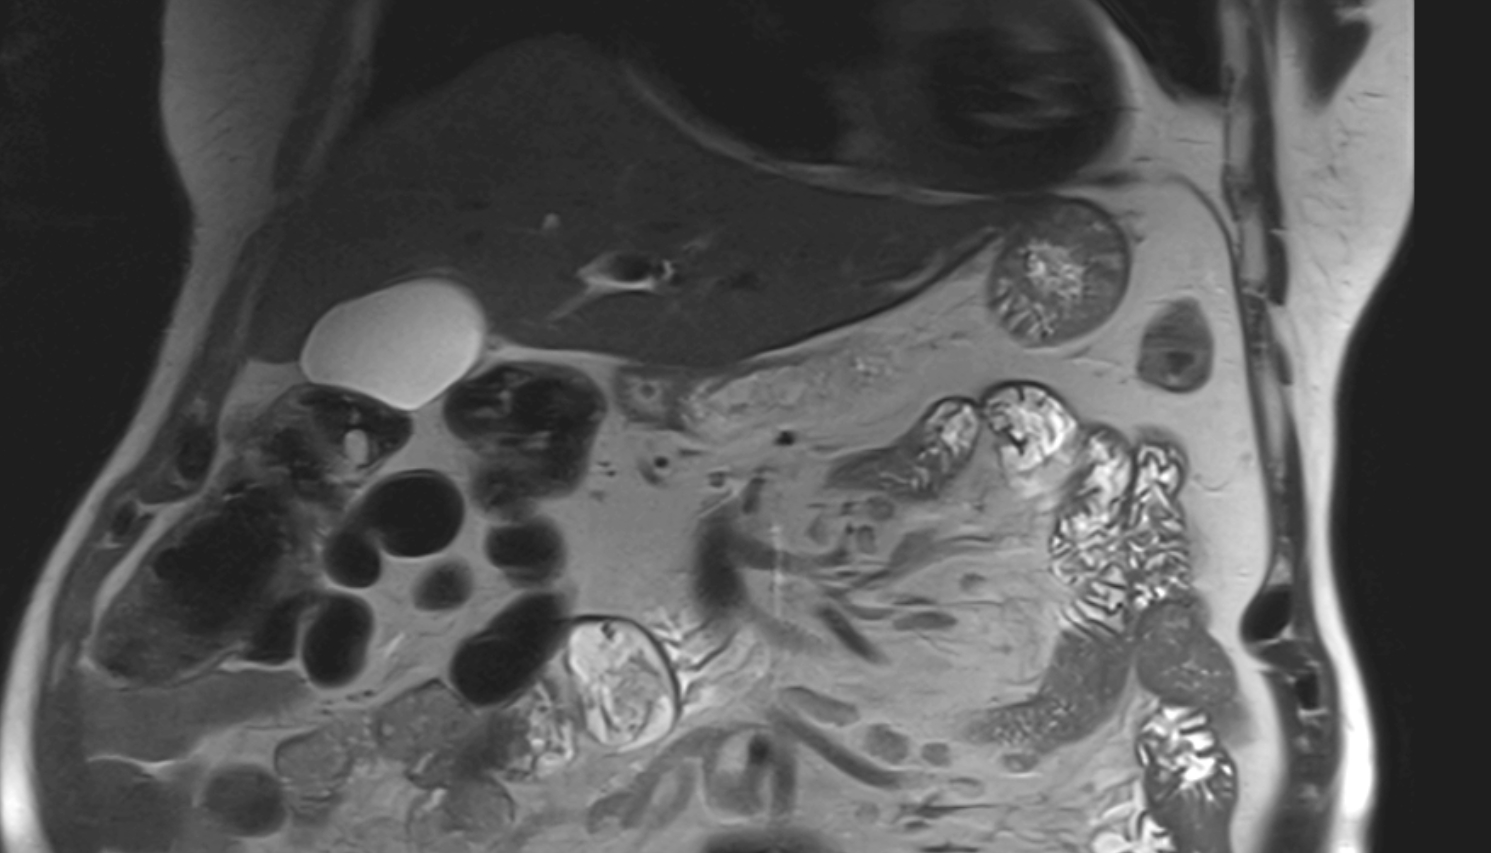

- kidneys

- Right kidney

- Left kidney

- Kidney cortex (Renal cortex)

- Renal capsule

- Renal medulla

- Renal pyramids

- Placenta

- Uterus (pregnancy)

- Amniotic fluid

- Umbilical cord

- Maternal ovaries

- Fetal kidneys